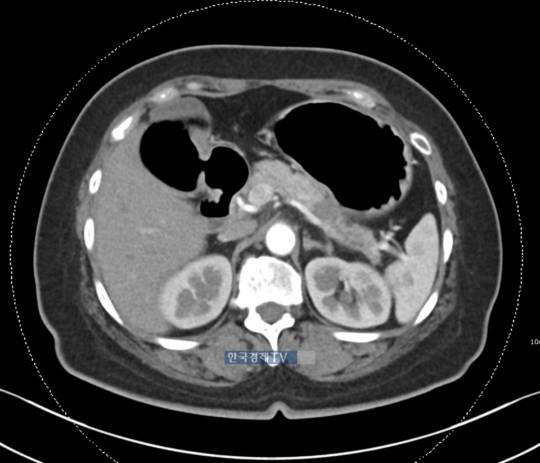

조영제를 사용한 CT 촬영이 '췌장암 검진을 위해 정기적으로 찍기는 과하다'는 입장도 있다.

전문의 C씨는 "보통 조영제를 사용한 CT 촬영으로 췌장암인지 확인하는데, 막연한 걱정으로 CT를 찍기엔 부작용 우려가 크다"며 "촬영에 사용하는 조영제 때문에 두드러기부터 급성콩팥병, 알레르기 쇼크를 일으키는 사람도 있으며, 촬영 과정에서 불필요하게 방사선에도 노출된다"고 말했다. CT 조영제 부작용은 적지 않아 사용 전 동의를 받을 정도며, 이로 인해 사망한 경우도 있다.